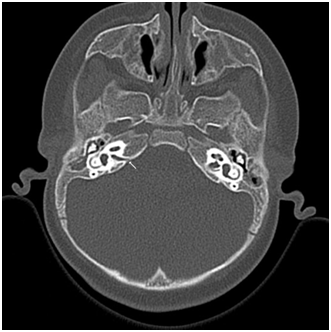

A dysmorphism of the corpum callosum and subependimal noduli near the trigonus and in the posterior segment of the right temporal lobe was shown. The MRI results suggested a final diagnosis of pontine cap dysplasia (PTCD) and periventricular nodular heterotropia (PNH) (Figure 2&3). To exclude that the behavioral responses depended from saccular hearing, further the cervical-vestibular evoked myogenic potentials (cVEMP) were measured to assess the presence of saccular and vestibular nerve responses were present but with low amplitude on the left side, while they were absent on the right side.

Figure 2 Saggital T1-weighted MRI image showing dysmorphism of the dorsal upper pons proteding in the fourth ventricle, flattening of the ventral pons.